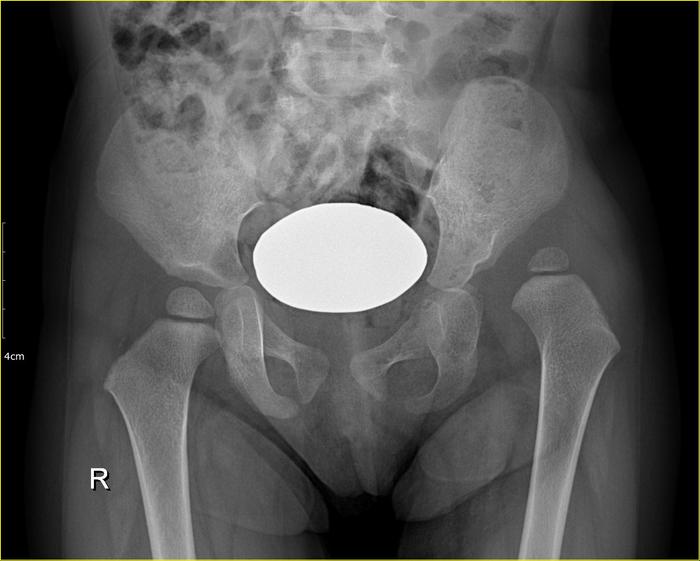

도수 검사의 이학적 소견과 방사선학적 소견으로 진단할 수 있다. 1. 이학적 검사 1) 오톨라니(Ortolani) 검사: 탈구된 골두를 골반의 제 위치에 집어넣었을 때 느껴지는 이상 마찰음을 확인하는 검사법으로, 아이를 바로 눕힌 뒤 고관절을 90도로 구부리고 무릎 관절은 완전히 구부린 다음, 허벅지를 벌리면서 대퇴골두 부위를 앞쪽으로 밀어 올리면 “뚝”하는 관절이 비구(대퇴골두가 들어가야 할 골반 부위) 내로 맞게 들어가는(정복되는) 느낌이 손 끝에 촉지된다. 2) 발로(Barlow) 검사: 탈구를 유도하여 탈구성 관절을 진단하는 검사법으로 고관절을 벌린 상태로 90도 구부린 후 허벅지를 모으면서 바닥에 평행하게 바깥쪽으로 대퇴골두 부위을 밀어내어 탈구를 유도한다. 2. 방사선 소견 생후 4~6개월까지는 단순 방사선 검사는 진단에 큰 도움이 되지 않는다. 대퇴골두가 아직 연골 상태이며 비구를 비롯한 골반골의 많은 부분이 연골로 되어 있기 때문에 방사선 사진에는 보이지 않기 때문이다. 이 시기를 넘어서 대퇴 골두의 골화가 시작되면 단순 방사선 검사를 통하여 진단할 수 있는데, 비구 경사각의 증가, 대퇴골두 골단의 출현 지연이나 저형성 및 탈구 소견 등을 확인할 수 있다. 생후 4~6개월 이전에는 초음파 검사가 가장 정확한 검사법이다. 관절의 탈구 여부, 탈구 정도, 탈구 유발 여부, 비구 이형성 정도 등 유용한 정보를 얻을 수 있다. 조기 진단 및 신생아 선별 검사(screening test)로 사용되며, 보장구 등을 이용하여 치료 경과를 계속적으로 감시하는데 사용된다. 그러나, 검사 결과가 민감하기 때문에 특히 신생아에서는 판독에 유의하여야 한다.